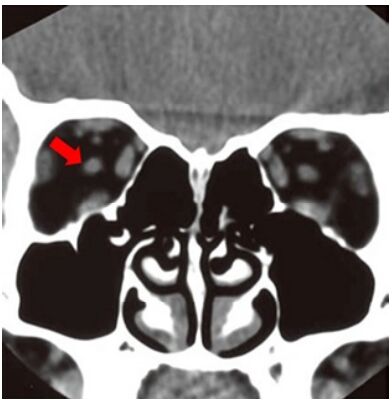

35.下圖箭頭處所指為下列何者?

(A)medial rectus muscle (B)superior ophthalmic vein (C)optic nerve (D)lateral rectus muscle